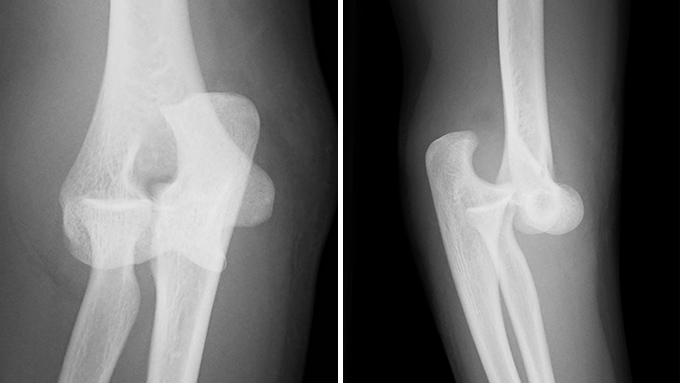

肘関節脱臼

転倒やスポーツ中の転倒で手をついたときなどに、肘の骨同士が外れてしまう外傷です。最も多いのは後方脱臼で、激しい痛みと腫れ、変形を伴い、肘を動かすことができなくなります。治療はまず整復(脱臼を戻すこと)を行い、骨折や靭帯損傷の有無をCTやMRIで精査します。関節が安定していれば一時的な固定後に可動域訓練を始め、靭帯損傷が強い場合は手術で修復します。早期に適切な治療を行うことで後遺障害を最小限に抑えることができます。

症例 10代後半 女性(保存加療)

(受傷時)

(受傷後 16か月)